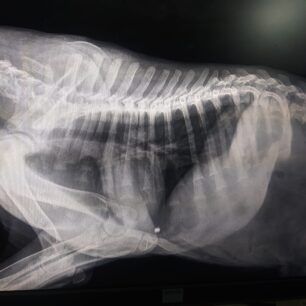

Στις ακτινογραφίες που διενεργήθηκαν ανευρέθηκε βλήμα αεροβόλου όπλου στη θωρακική κοιλότητα οπισθοστερνικά, έντονα ελαττωμένη οστική πυκνότητα ιδιαίτερα στα οπίσθια άκρα, αξιοσημείωτη χαλαρότητα αμφοτερόπλευρα και στα δύο γόνατα πού συνάδει με εικόνα ρήξεως πρόσθιου χιαστού. Στην ουσία όπως θα δείτε και στις ακτίνες μετά από ένα σημείο το στο σχεδόν παύει να υπάρχει, αν όχι από όταν γεννήθηκε τότε στην πορεία το ζώο όσο πιο ατρωφικο γινόταν το οστό τόσο τον οδηγούσε στην κατάσταση που είναι τώρα. Ο Αslan έχει 10% πιθανότητες όχι να περπατήσει αλλά να σταθεί, παρόλα αυτά δεν θα τα παρατήσουμε αφού έχει μια ζωντάνια και μια θέληση για ζωή που θαυμάζω μετά όλο αυτό που του συνέβη στους 5 μήνες της ζωής του ... Θα ακολουθήσουμε φαρμακευτική αγωγή για την θρέψη των οστών και σε 1 μήνα θα πρέπει να πάμε ξανά να δούμε πως πάμε! Για όποιον θέλει να βοηθήσει αυτοί είναι οι λογαριασμοί του κτηνιάτρου κ Νίκου πατσινακιδη.